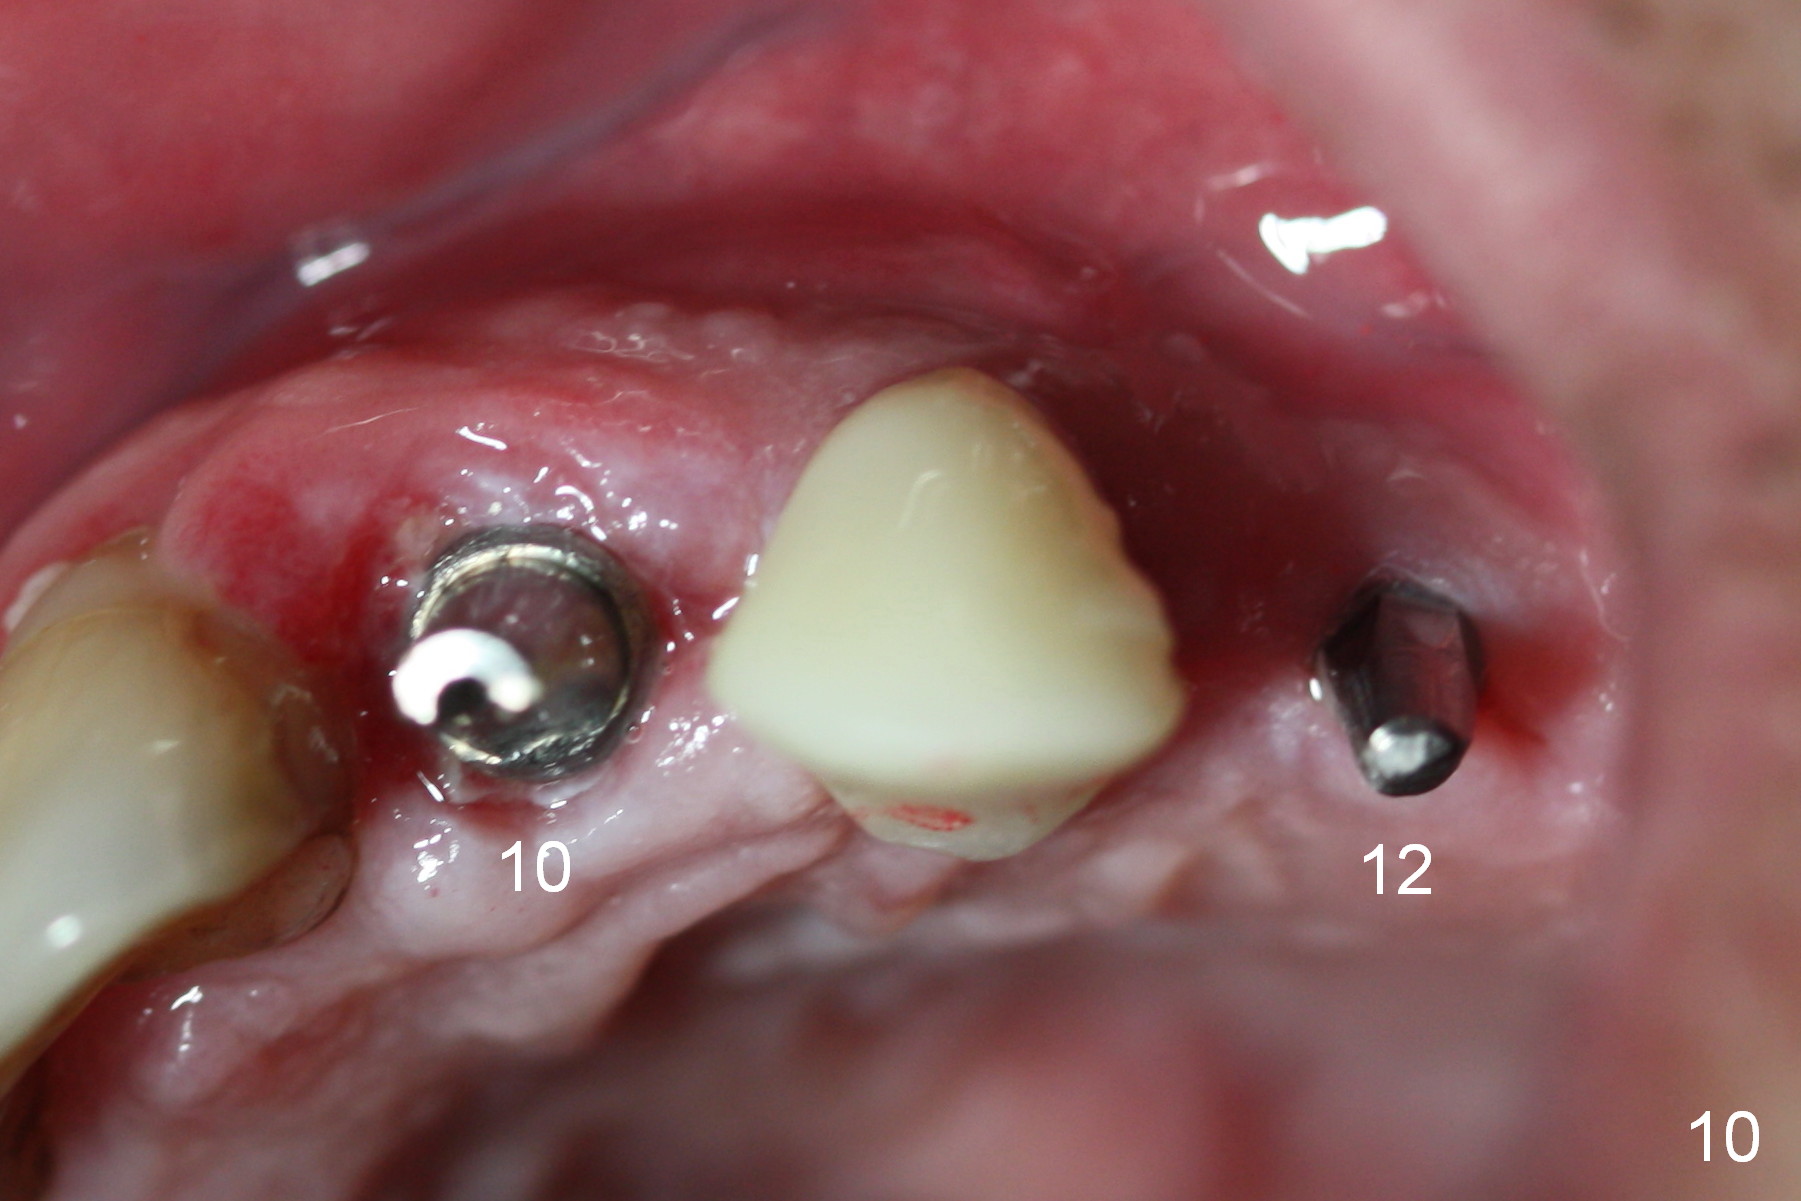

When the patient returns for implant placement (2nd visit after initial exam), he reveals that he is a dental phobic.  He requests placement of 4 implants in the upper left quadrant, instead of 2.  Narrow ridge is unexpected in the canine and premolar area (Fig.1).  Limited bone height at #13 (Fig.3 arrowheads: sinus floor) is found when initial drills are in place (Fig.2,3).  A 2-piece implant (4.5x17 mm tissue-level) is placed at #10 after extraction, while 1-piece implants are placed at 11 (3x17 mm (tissue-level, 15 °) and 12 and 13 (bone-level, 2.5x14, 12 mm, respectively; Fig.4,5).  In fact the 1 piece implant at #13 is not completely placed (Fig.5).  It is removed, the apical 3 threads are cut off (Fig.6 <, since a shorter implant was unavailable in the office) and the remaining implant is re-inserted.  The insertion torques of the 4 implants are ~ 60, ~ 35, < 35 and 15 Ncm, respectively.  After adjustment (Fig.7), immediate provisionals are fabricated at #10 and 11 (Fig.8, later splinted with composite), while perio dressing is applied around the implants at #12 and 13 and the provisionals at #10 and 11.  There is no nasal hemorrhage postop.  Although the perio dressing is loose 1 week postop (Fig.9), it is not removed.  When the upper lip fissure (Fig.9 <) heals, provisionals at #12 and 13 are planned to be splinted to the other two ones.  Two weeks postop, the upper lip fissure heals, the perio dressing dislodges and the implants at #12 and 13 are stable (Fig.10).  After abutment height adjustment, a splinted provisional is fabricated over these 2.5 mm 1-piece implants (Fig.11).